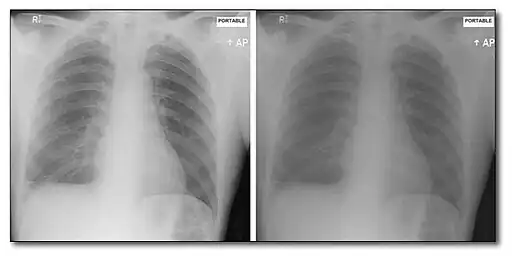

This form of image data processing is illustrated in the following figure:

A chest radiograph acquired at 56 kVp is shown in the top left panel of the figure. This is referred to as a low energy image. In the top right panel is a radiograph of the same patient's chest acquired at a high energy – 120 kVp, with 1 mm copper filtration. Results of the dual-energy processing are shown on the bottom row. The bone-subtracted image is shown in the bottom left panel and the tissue-subtracted image in the bottom right panel. Notice that the tissue-subtracted image demonstrates that the lesion in the patient's left lung is a calcified nodule, since it doesn't appear in the bone-subtracted image.